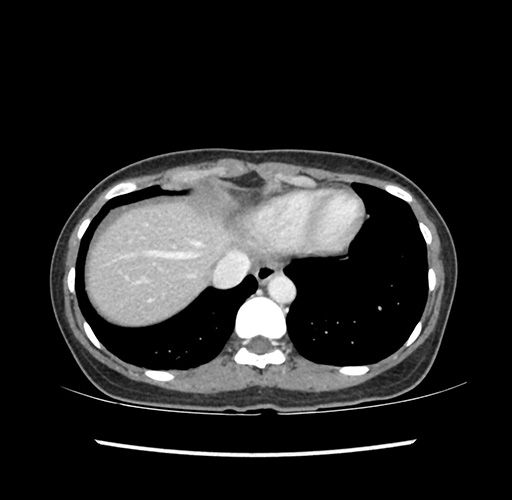

Imaging Analysis

Look through the patient's CT scan to identify any areas of concern for the necessary procedure.

Based on your CT findings, which issue(s) would give reason for "planned slowing down moment(s)" in this case?

Considering a standard left lateral sectionectomy procedure, what step(s) of the operation would you do differently in this case ?